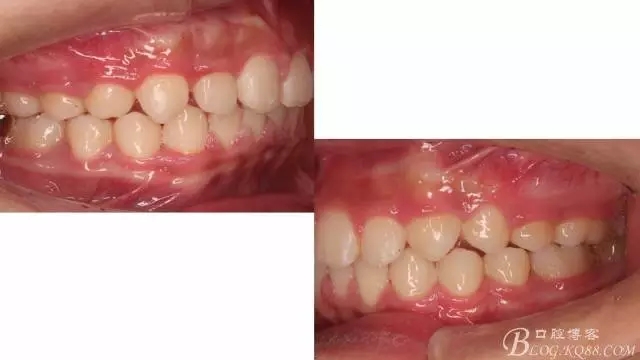

看看口內(nèi)照吧!真象“大暴牙”v假象“大暴牙”

三度深覆合,三度深覆蓋,尖牙,磨牙均二類關(guān)系!

術(shù)前側(cè)貌,下合后縮還算明顯,正面照有點看不出的樣子!